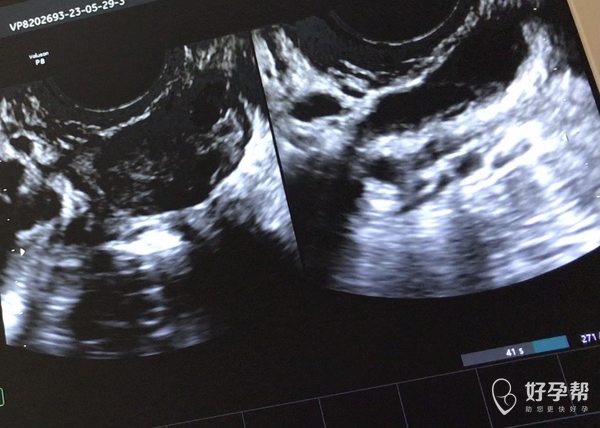

月经期查b超见图片是否提示输卵管积水还有什么

B超要图片和报告结合看,超声医生最清楚,这样留下的固定图片不能反应真实情况目前图片反应的是有盆腔积液,子宫未见异常,输卵管积液不好说,超声留的切面不好确定